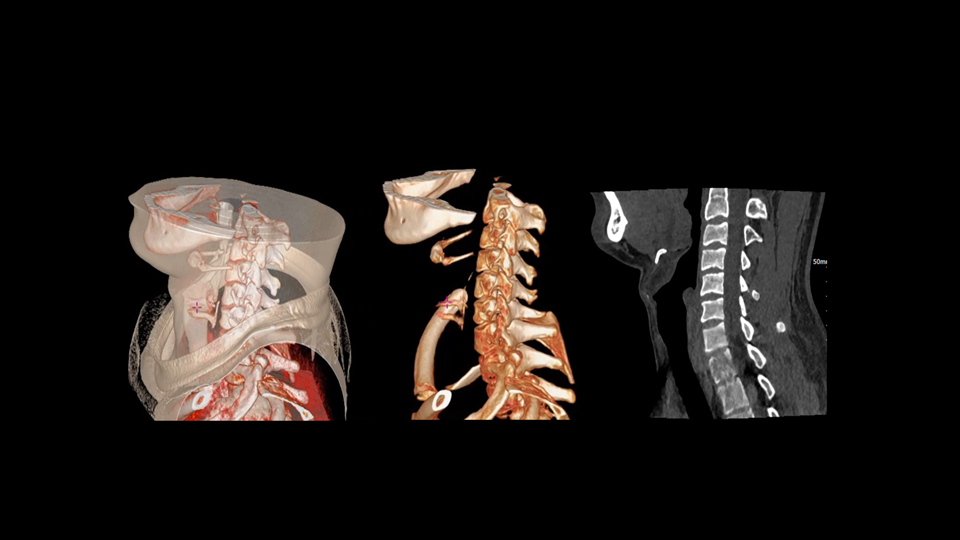

全身各部位动态CT成像

uCT SiriuX® 以16cm超宽Z轴覆盖,使超高时间分辨率应用于完整器官成像。无论是心脏搏动还是关节运动,整个目标区域可在同一瞬时被完整、清晰地捕捉,彻底消除时序误差,实现从“局部瞬间”到“全器官瞬时”的成像跨越。

全器官同步